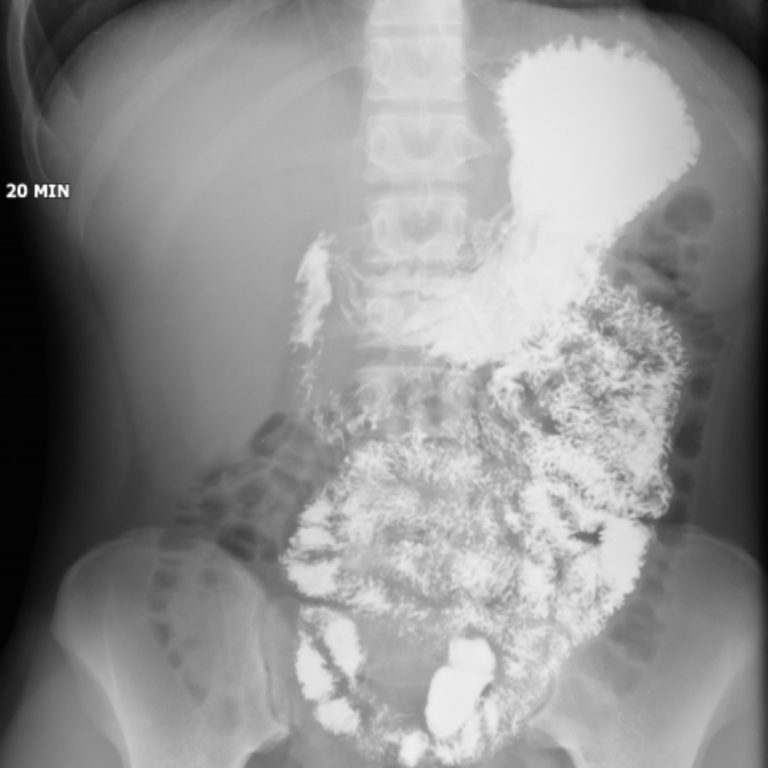

İNCE BARSAK GRAFİSİ

İnce barsakların kontrast madde içirilmesi (ince barsak pasaj grafisi) veya hastaya yutturulan bir tüp aracılığıyla hava ve kontrast madde verilmesi yoluyla (enteroklizis) incelenmesidir. Öncesinde hazirlik gereklidir. Tetkikten önceki 2 gün boyunca, hasta sulu gıdalar almamalıdır. Tetkik öncesinde, en az 12 saatlik açlık ve barsak tamizliği için müshil kullanimı gereklidir.

İnceleme nasil yapılır ?

Hastaya baryumlu kontrast madde içirilerek maddenin ince barsaklarda ilerleyisi doktor tarafindan ekranda izlenir. Kontrast madde kalin barsaklara kadar ilerler ve bu esnada çesitli pozisyonlarda filmler çekilir (Ince barsak pasaj grafisi). Ayrica daha detayli inceleme gerektiren durumlarda hastaya burnundan ince bir tüp yutturulur. Bu tüp, oniki parmak barsagina yerlestirilir ve tüpten kontrast madde ile birlikte hava verilir. Bu sekilde filmler alınır. Çekimin süresi, verilen kontrast maddenin kalin barsağa geçis süresine göre değisir.

Kontrast maddenin çekuma geçiş zamanı tabiidir. İnce barsak segmentlerinin lokalizasyonu mukozal yapısı tabiidir. Duodenum, jejenum genişliği, konturları ve pili yapısı tabiidir. Dolum defekti veya fazlalığı saptanmamıştır. Flokülasyon, segmentasyon ve fragmantasyon izlenmemiştir Terminal ileum kalibrasyonu normal sınırlar içinde olmakla birlikte mukozasında ödematöz paterne ait görünüm dikkati çekmektedir.